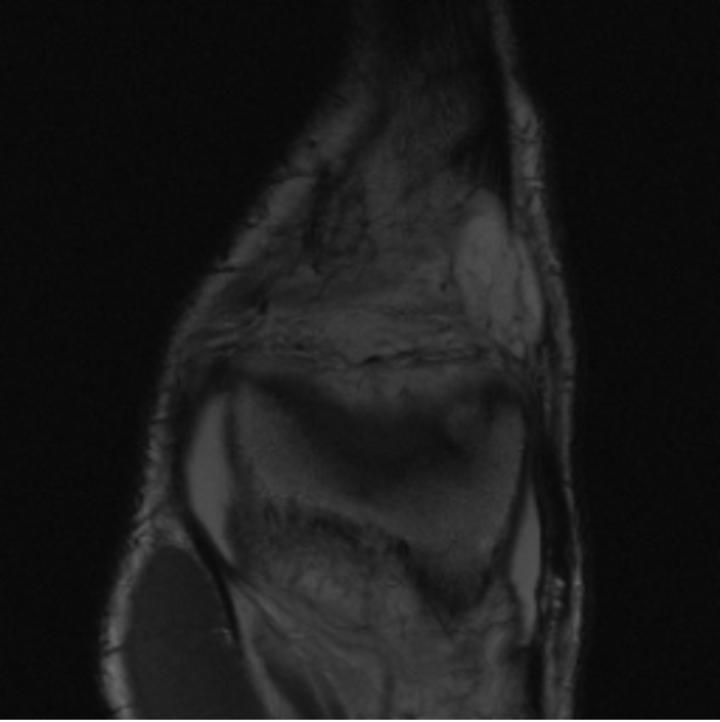

5.3 Out-of-Domain Generalisation

One way to test the generalization capability of the trained X-Diffusion is to test it on a completely different domain from an MRI dataset not seen during training. We report the single-slice results on the test set of knees from NYU fastMRI [33, 80], using the X-Diffusion trained on the BRATS brain MRIs. The test PSNR result is 34.17 and an example is shown in Figure 8. It shows how successfully X-Diffusion can generate knee MRIs (out-of-domain) despite being trained on brains.